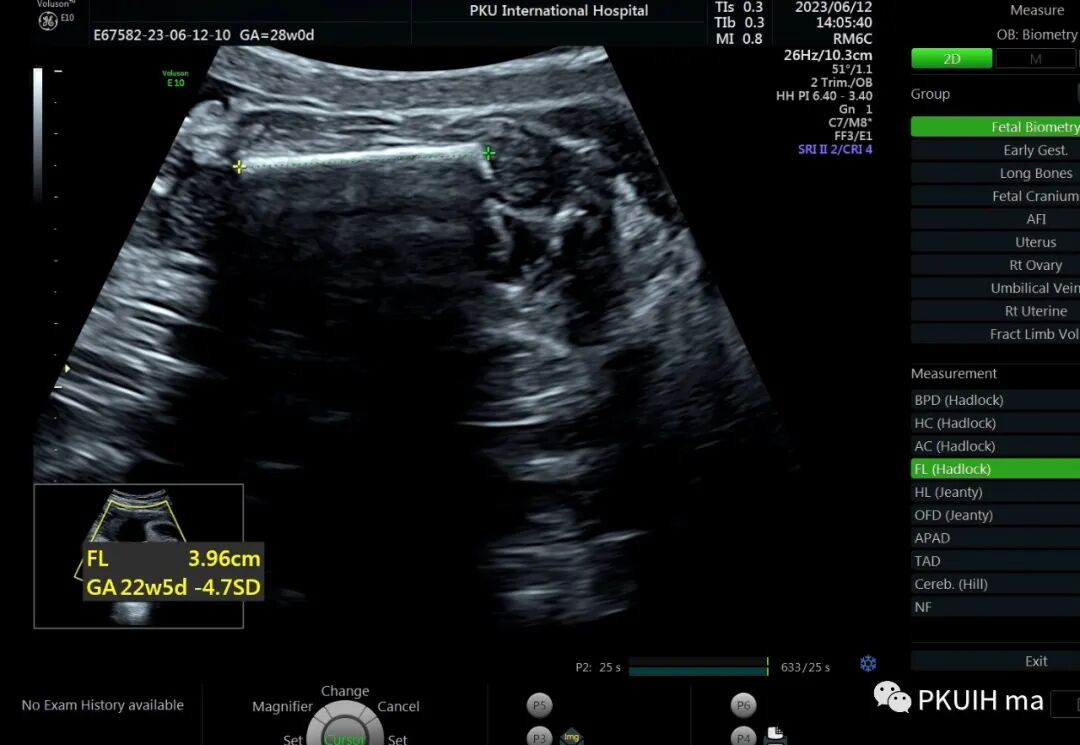

孕23周常规筛畸发现四肢长骨偏短,孕妇月经正常,核对早孕超声,孕周也没问题。

24周+复查发现还是肢体短,生长变慢

28周检查发现肢体越来越短

36周检查发现肢体越来越短,股骨和肱骨只相当于25-6周

大多数孕期发现的骨骼发育不良通常表现为严重的短肢畸形,但足底长度通常不受累。正常时股骨长/足底长度约1:1,<0.87,考虑骨骼发育不良,同时在FGR的诊断中也有帮助。产前超声诊断的主要目的是识别出致死性的骨骼系统发育异常,对临床起到指导意义。区分致死和非致死性骨骼发育异常的主要超声指标有:1、严重的四肢短肢畸形,四肢所有长骨均低于该孕周平均值4个标准差,或股骨长度/胸围<0.16。2、严重的胸廓狭窄:胸围<胎龄的第5百分位,心胸比>0.6(一定要先除外心脏畸形),胸围/腹围比<0.89。3、某些特殊征象,比如严重的颅骨“三叶草样”畸形。